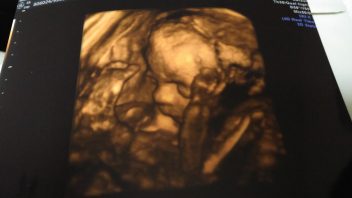

V pátek jsem byla objednána na ráno ke své gynekoložce. Manžel mne naštěstí k lékařce odvezl autem. Ještě v autě jsme si dělali srandu, že příště musím návštěvu posunout, alespoň na půl devátou, protože časné ranní vstávání nám nedělá dobře. 🙂 Paní doktorka mne vyšetřila a zkonstatovala, že čípek je v pořádku, ale hlavička miminka je hodně sestouplá. Takže mi doporučila se víc šetřit a odpočívat, napsala mi magnezium a kvůli nižší hladině železa v krvi, které odhalili krevní testy, také železo. Podívala se ještě na prcka na UTZ. Měla jsem radost, že ten náš poklad opět vidím. Paní doktorka popisovala vše, co vidí, a vůbec byla důkladná. Vtipné bylo, že jsem chtěla fotečku našeho pokladu, protože poslední mám z 3D UTZ. Paní doktorka udělala fotku obličeje, ale já na ní nebyla schopná nic poznat. Ukazovala mi, kde jsou oči, nos a ústa, ale já tam prostě neviděla nic. Přitom srdíčko jsem poznala hned, páteř také, ale ten obličej jsem prostě tentokrát nebyla schopná identifikovat, takže fotečku nakonec nemám. 🙂 Další návštěva za 14 dní, tentokrát ještě před osmou hodinou, jinak to bohužel nešlo, a bude to již poslední kontrola u mé lékařky. Další kontrola bude už v poradně nemocnice. Čas se nám krátí.